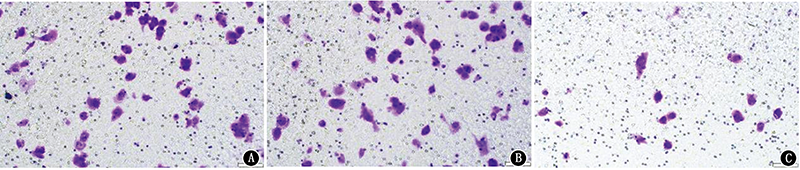

Abstract: Objective To investigate the effects of programmed death-ligand 1 (PD-L1) expression on the biological behaviors of gastric cancer cell line MKN45. Methods The PD-L1 gene of gastric cancer cell line MKN45 was silenced by RNA interference technique. MKN45 cells were divided into blank control group, si-NC group (transfected with siRNA-NC) and si-PD-L1 group (transfected with siRNA-PD-L1). Quantitative real-time PCR was used to detect the mRNA expressions of PD-L1 and epithelial-mesenchymal transformation (EMT)-related proteins E-cadherin, Vimentin and Snail in MKN45 cells, and Western blotting was used to detect the expression levels of PD-L1 protein in MKN45 cells of each group. Transwell migration test, Transwell invasion test and MTT test were used to detect the migration, invasion and adhesion abilities of MKN45 cells. Results The relative expression levels of PD-L1 mRNA in the blank control group, si-NC group and si-PD-L1 group were 1.002±0.092, 1.005±0.121 and 0.237±0.017, respectively, with a statistically significant difference (F=75.61, P<0.001). The protein expression levels of PD-L1 in the three groups were 0.944±0.028, 1.008±0.088 and 0.269±0.015, respectively, with a statistically significant difference (F=172.99, P<0.001). The mRNA and protein expression levels of PD-L1 in the si-PD-L1 group were lower than those in the other two groups (all P<0.001), but there were no statistically significant differences between the blank control group and si-NC group (all P>0.05). The cell migration rates of the blank control group, si-NC group and si-PD-L1 group were (1.000±0.020)%, (1.012±0.084)% and (0.488±0.050)%, respectively, with a statistically significant difference (F=80.73, P<0.001). The cell invasion rates of the three groups were (0.929±0.087)%, (0.924±0.208)% and (0.300±0.100)%, respectively, with a statistically significant difference (F=19.37, P<0.001), and the cell adhesion rates of the three groups were (100.000±5.407)%, (99.280±4.845)% and (59.723±2.674)%, respectively, with a statistically significant difference (F=79.87, P<0.001). Compared with the blank control group and si-NC group, the migration, invasion and adhesion abilities of MKN45 cells in the si-PD-L1 group decreased significantly (all P<0.001). The expression levels of E-cadherin mRNA of the three groups were 1.000±0.023, 0.981±0.051, 3.618±0.201, the expression levels of Vimentin mRNA were 1.000±0.043, 1.108±0.150, 0.328±0.011, the expression levels of Snail mRNA were 1.061±0.103, 1.090±0.110, 0.304±0.043, respectively, with statistically significant differences (F=477.17, P<0.001; F=65.97, P<0.001; F=72.70, P<0.001). Compared with the blank control group and si-NC group, the mRNA expression levels of Vimentin and Snail of MKN45 cells in the si-PD-L1 group decreased, while the expression level of E-cadherin mRNA increased, with statistically significant differences (all P<0.001). Conclusion Silencing the expression of PD-L1 can reduce the migration, invasion and adhesion abilities of MKN45 cells, and the mechanism may be related to the effect of PD-L1 on the EMT pathway of gastric cancer.